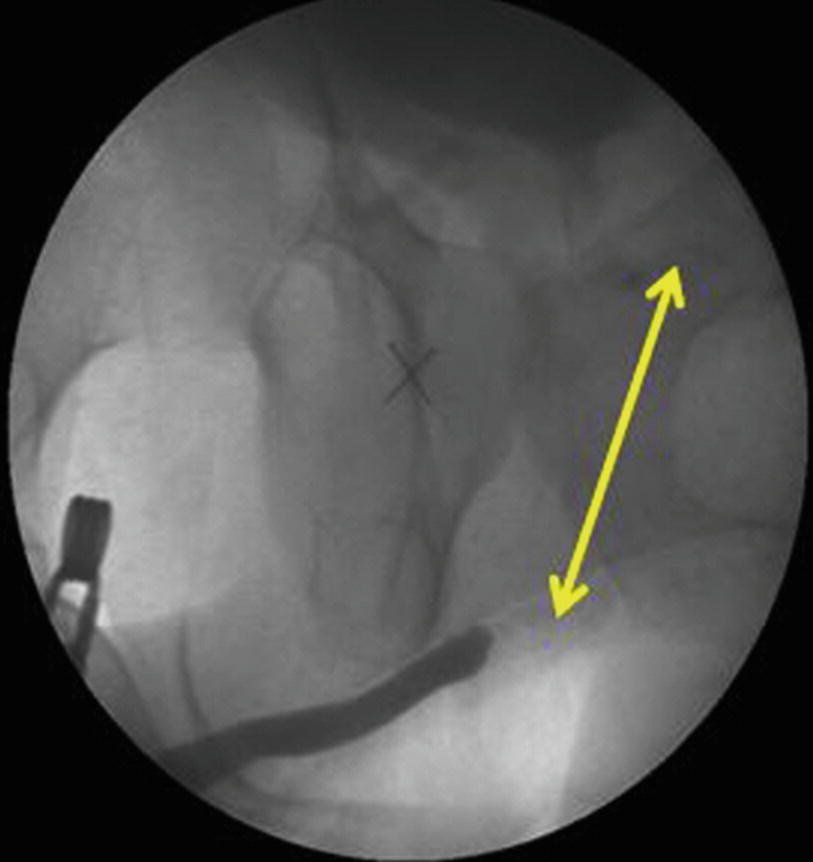

RGU and MCUG depicting bulbar urethral ischemic necrosis (BUIN)

Patient selection for these procedures is of paramount importance. The key is to evaluate which patient would benefit from urethral substitution using a bowel segment. The next challenge is to find the best suited bowel segment for the reconstruction. Usually the bowel segment with pedicle closest to the prostate is suitable. The preferred choice is the use of sigmoid colon. Patients need to admitted a day prior to urethroplasty. Bowel preparation is given and may include enema. Preoperative intravenous prophylactic antibiotics are started. Urethroplasty usually starts with a perineal incision and dissection. The healthy end of anterior urethra is identified. Crural seperation and inferior pubectomy is performed as and when necessary. In our experience, these patients often have a high bladder neck requiring a transpubic approach. This is usually performed with a infraumbilical midline incision. The initial disssection is retroperitoneal. Posterior pubectomy is performed and scar tissue excised. The posterior urethra is incised on a bougie passed from the SPC tract. This avoids opening the bladder. Once the posterior urethra is adequately freed from scar tissue, assesement of length of gap is made. The sigmoid colon is mobilised on its mesentery. The lower protion of sigmlid colon needs to be sacrificied and the upper part is swinged down on its pedicle. The sigmoid is refashioned to 26-30 Fr on a Nelatons catheter. The tailored sigmoid segment is then transposed to the perineum through abdomino perineal window. We usually keep the arch of pubic bone intact and perform inferior pubectomy (from below) and posterior pubectomy (from above). The challange is in performing the anastomosis between proximal sigmoid end and bulbo membranous junction. One trick is to keep a guide wire across the anastomosis which helps in insertion of Foleys catheter. Anastomosis is performed with 4-0 Polydiaxone suture. The distal anastomosis is done from perineum. We have additionally always mobilised omentum and wrapped around the proximal anastomosis.Clear oral fluids are started on post op day 1 as per the latest protocol. We do not keep patients fasting. Abdominal drain is kept for 5 days and once bowel movements start, drain is removed.Full oral diet is started on day 5–6. Patients are discharged on day 6–8. Catheter is removed after 6 weeks. We perform pericatheter urethrogram before removal of catheter.